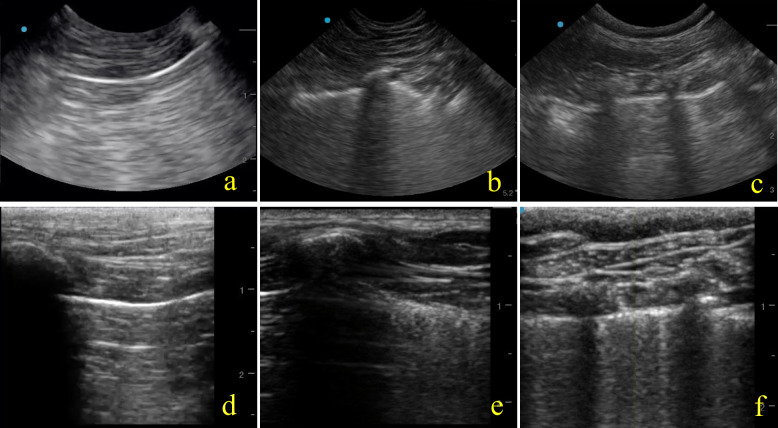

Results: Eighty-eight ultrasound clips from nine dogs were analyzed. HFLUT demonstrated strong inter-rater agreement in B-mode (κ = 0.89) and near-perfect agreement in M-mode (κ = 1.00) for pleural line homogeneity. In contrast, CUT showed minimal agreement in both B-mode (κ = 0.34) and M-mode (κ = 0.37). Homogeneous pleural lines were predominantly observed in control dogs or those with cardiogenic pulmonary edema (CPE), while non-homogeneous pleural lines were more common in dogs with non-cardiogenic alveolar-interstitial syndrome (NCAIS). Vertical subpleural fields identified in M-mode were associated with both CPE and NCAIS, whereas horizontal fields were more often observed in control dogs.

Conclusions: HFLUT offers superior inter-rater reliability for characterizing pleural and subpleural features in canine LUS compared to CUT, particularly in M-mode. These findings suggest HFLUT may enhance diagnostic accuracy for pulmonary conditions in dogs. Further studies are needed to explore the diagnostic potential of LUS in differentiating vertical artifact (e.g., B-lines) etiologies in veterinary patients.